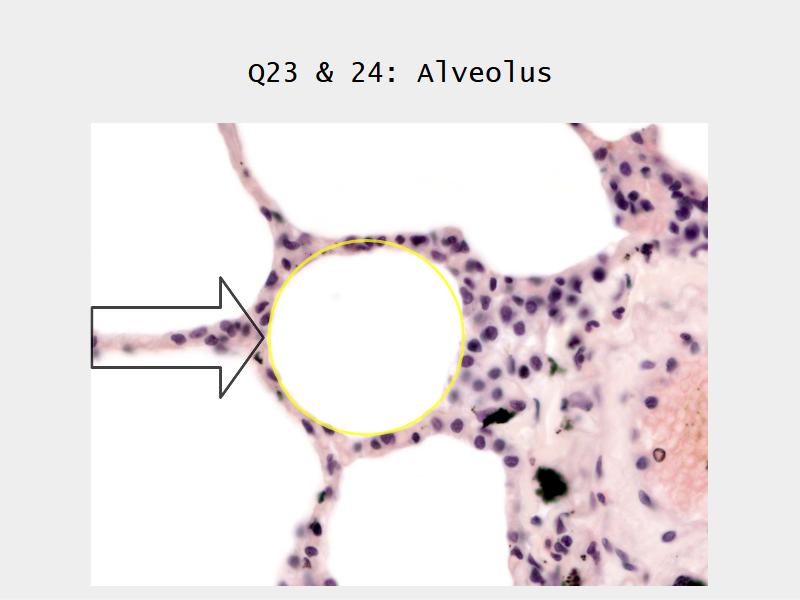

- Alveoli

Lungs